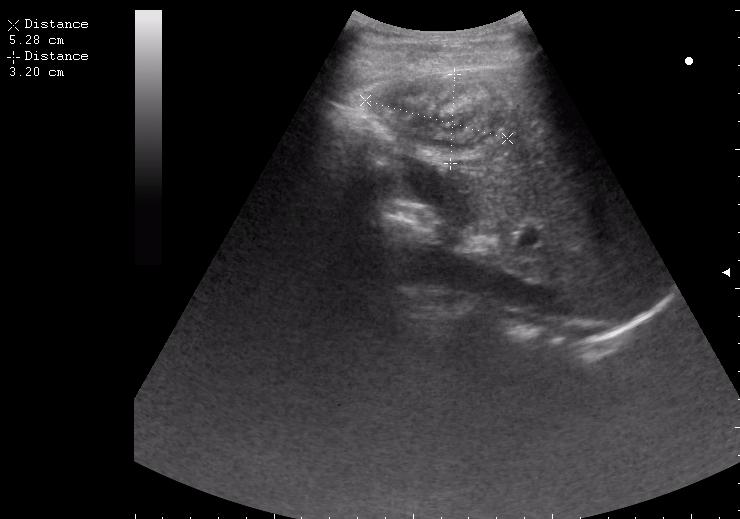

спустя 8 мес. после операции